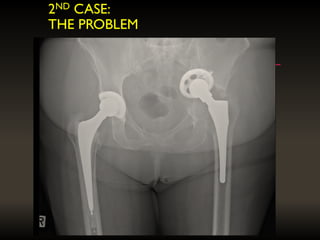

2ND CASE:

THE PROBLEM

THE BIO-MODEL OFTHE PELVIC DISSOCIATION AND IIIB OUTLINE OF THE PROPOSED IMPLANT Fracture line through posterior column = 2 parts THE NEED FOR CUSTOM IMPLANTS (HIP)